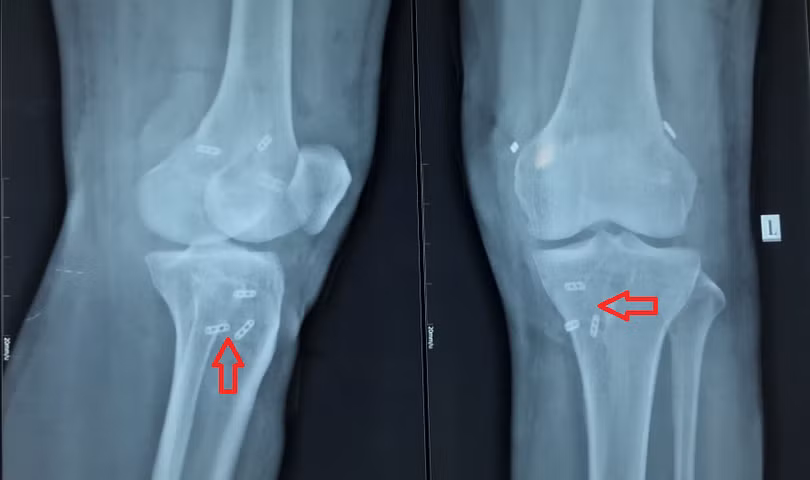

![]() |

| Vị trí các vòng treo gân và vít tự tiêu sau khi tái tạo 3 dây chằng chéo trước, chéo sau, bên ngoài |